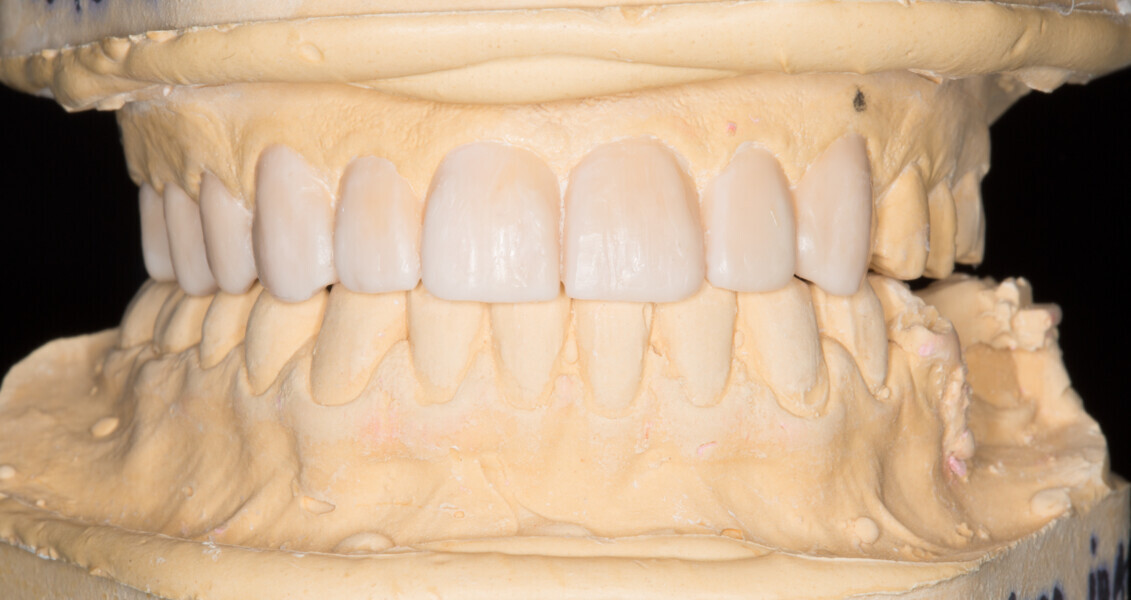

Fig. 5: Functional analysis wax-up.

Fig. 6: Functional analysis wax-up.

Fig. 7: Functional analysis wax-up.